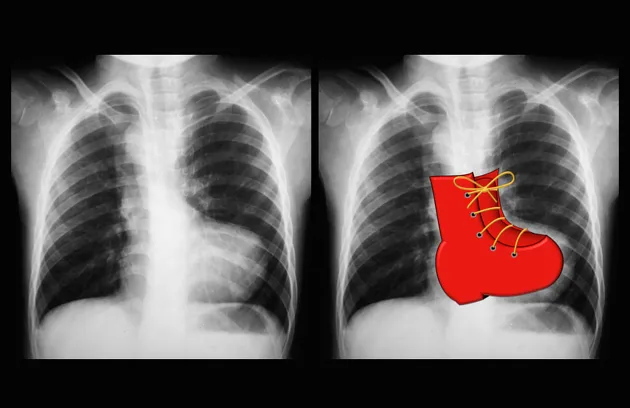

- Right Ventricle (RV): The cardiac apex is lifted upward, creating a "boot-shaped" heart. On a lateral view, it fills the retrosternal clear space.